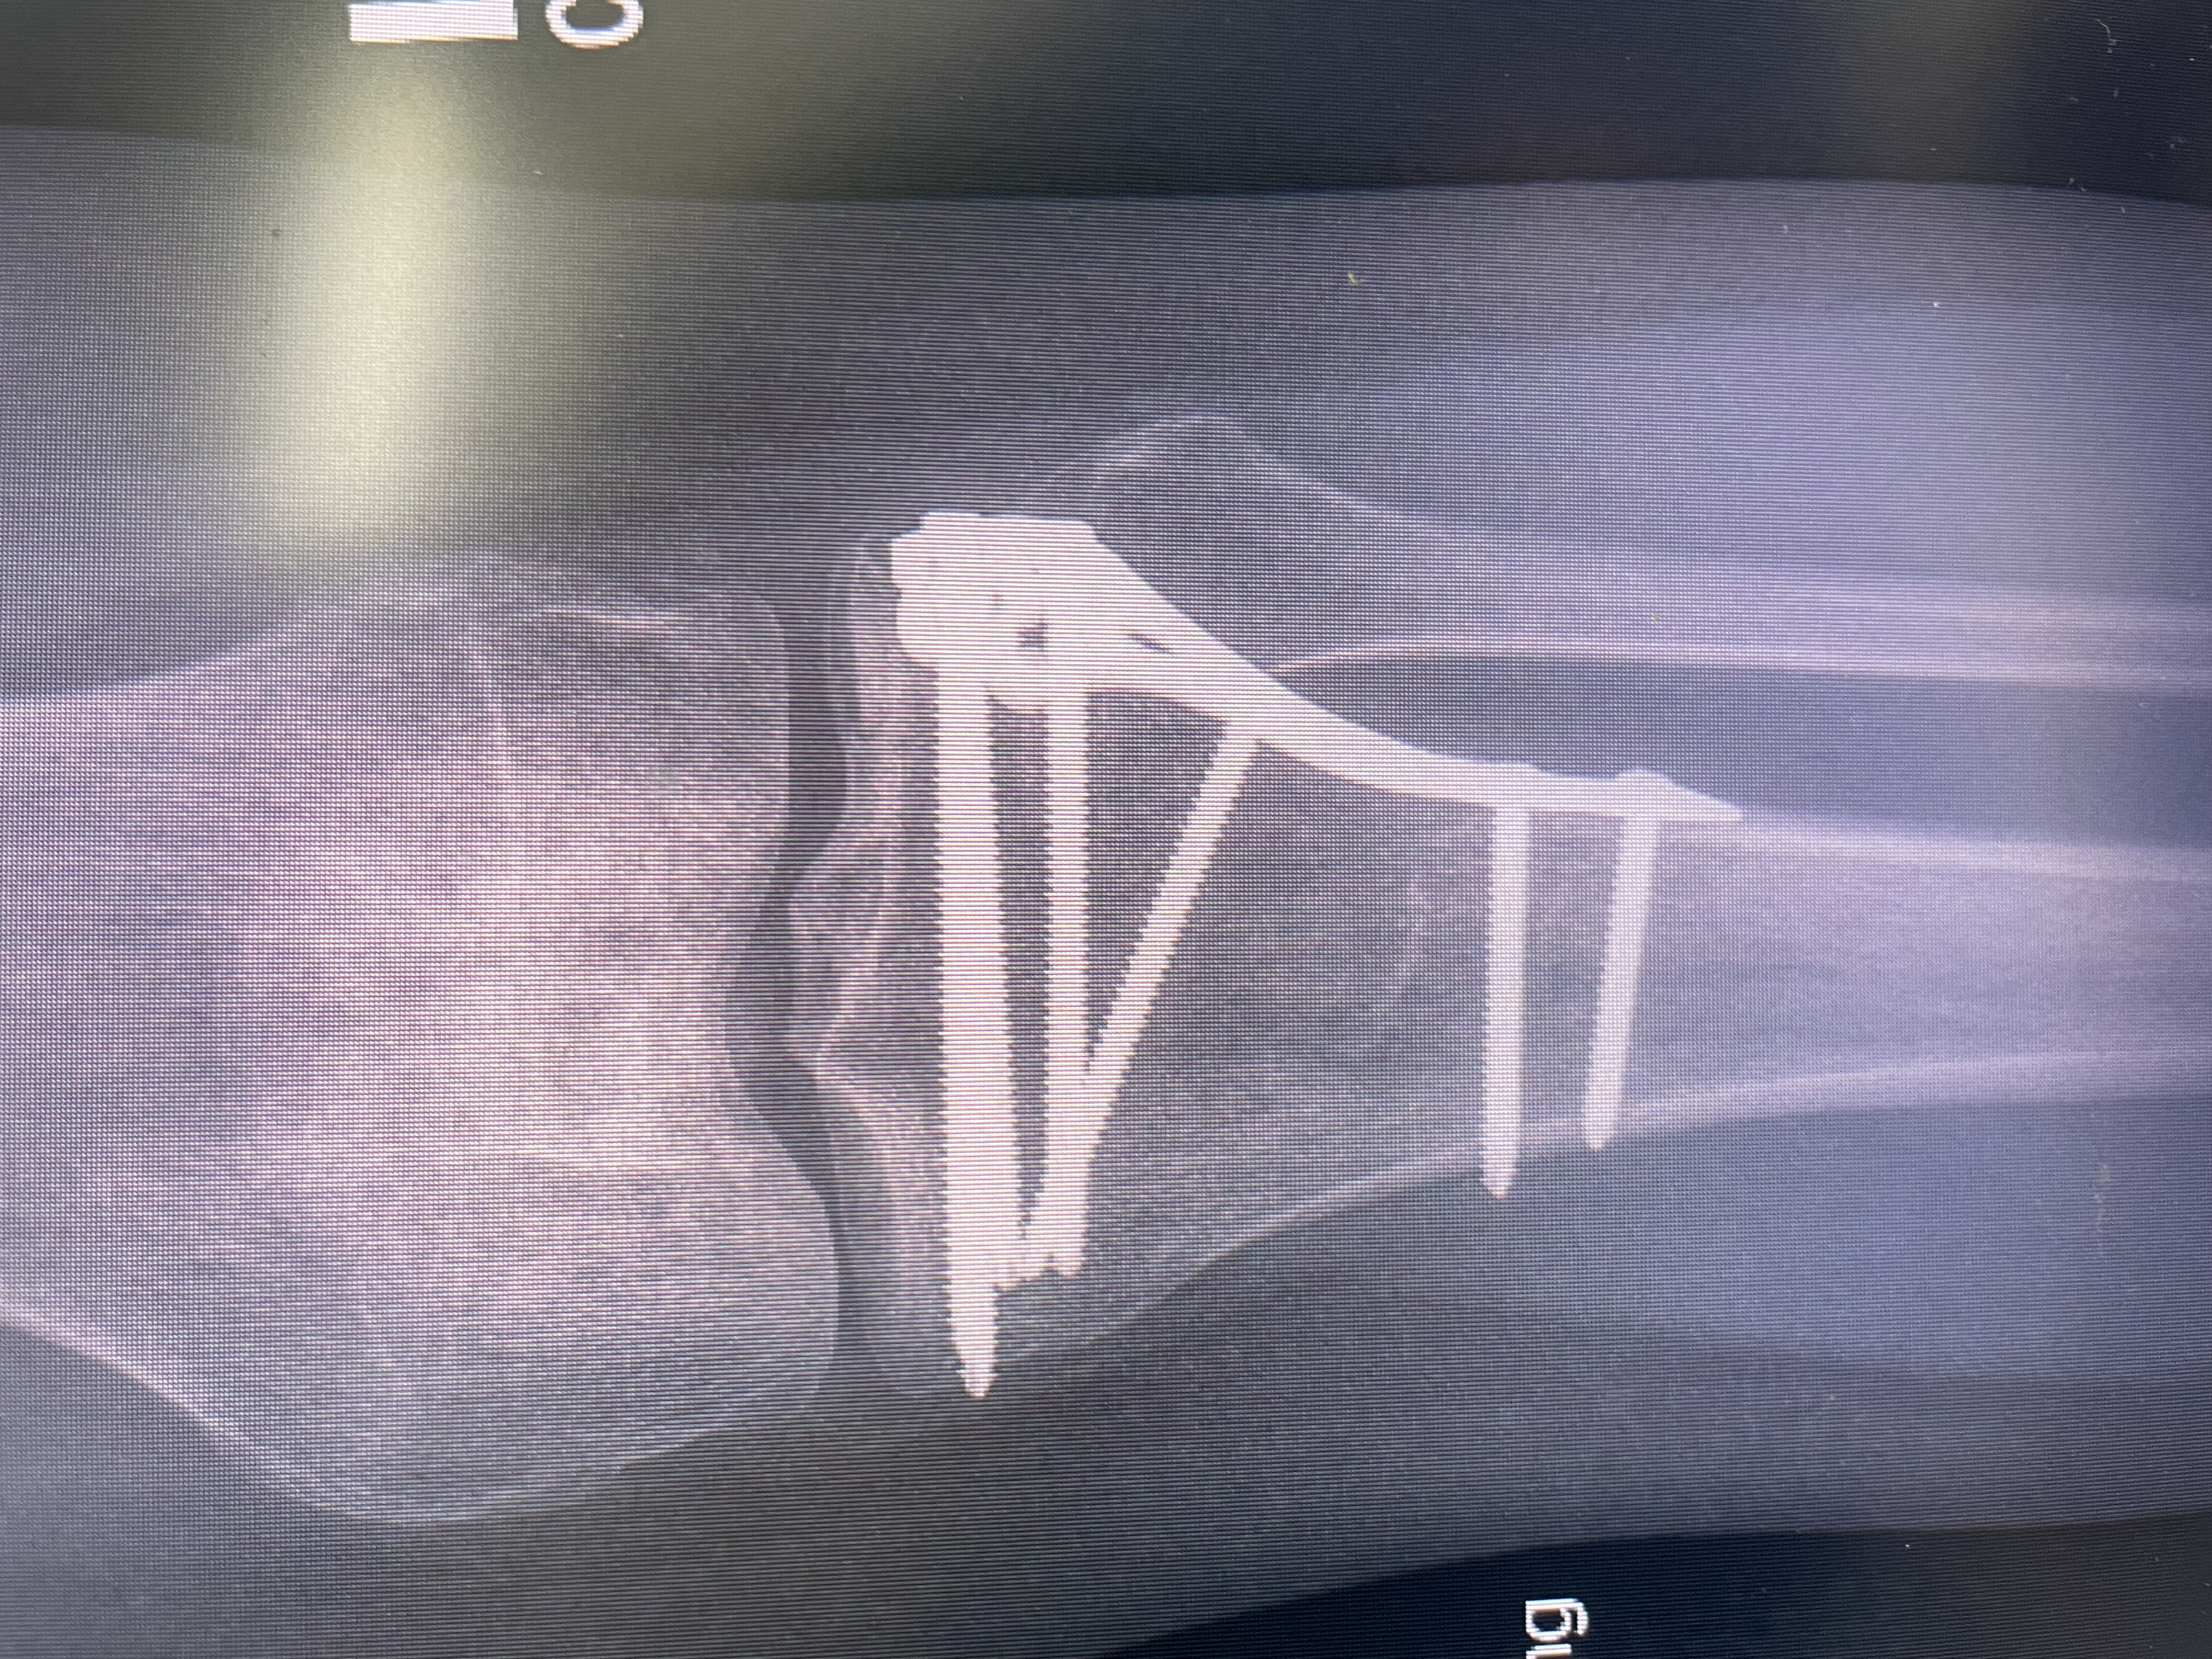

Last May, while I was out dog walking (my job and absolute passion!), one of my clients’ dogs accidentally crashed full speed into my leg. The impact was so strong it fractured my left tibia. I needed orthopaedic surgery to repair the break, and I now have a large metal plate and 8 screws holding my leg together.

Recovery hasn’t been easy. I’ve done everything I can to heal and get back to normal, but the metal hardware has been causing ongoing pain, discomfort, and limited mobility. My doctor has said I’m now eligible to have the plate and screws removed (YAY) — something I’ve been looking forward to for months.